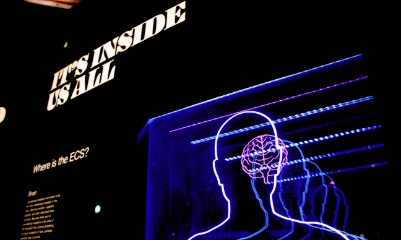

志御科技致力于成為全球肝

腦醫療AI領域的創新引領者

上海志御軟件信息有限公司(簡稱:志御科技)是中國領先的高科技醫療AI創新企業,創始團隊由知名醫學影像科學家隊伍及世界500強企業資深管理和營銷精英組成。公司致力于成為全球肝、腦醫學影像AI分析、AI輔助診斷以及AI遠程醫療的創新引領者,打造肝、腦醫療AI第一品牌。